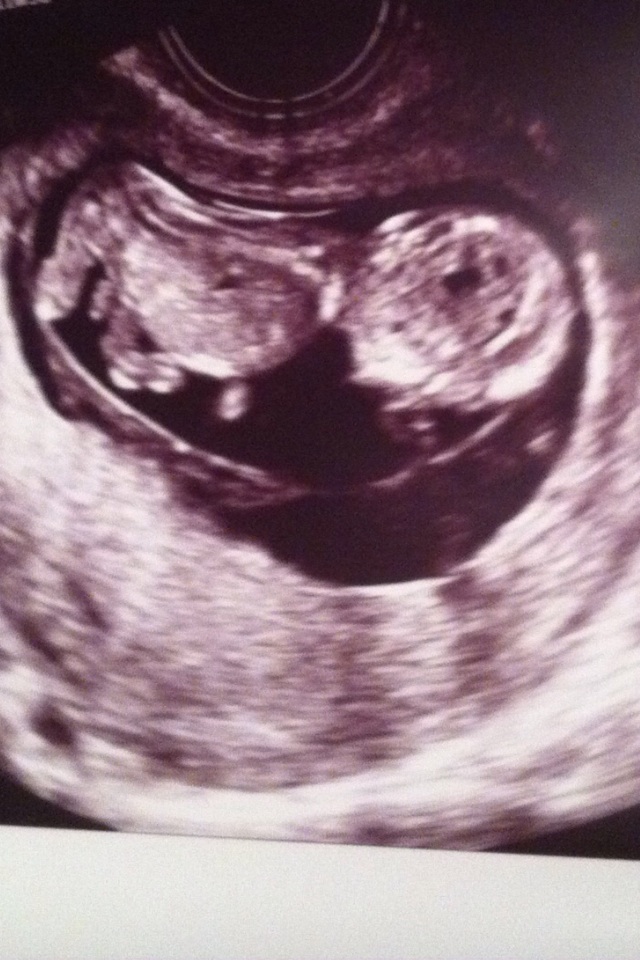

These are the two best images from my first ultrasound. Looked like a girl to me (rounded skull) in all the photos but one! (Sure you can tell!) Boy maybe? I've seen some confirmed girl ultrasounds around the same GA whose faces were pretty angular though..Guess for me? (: